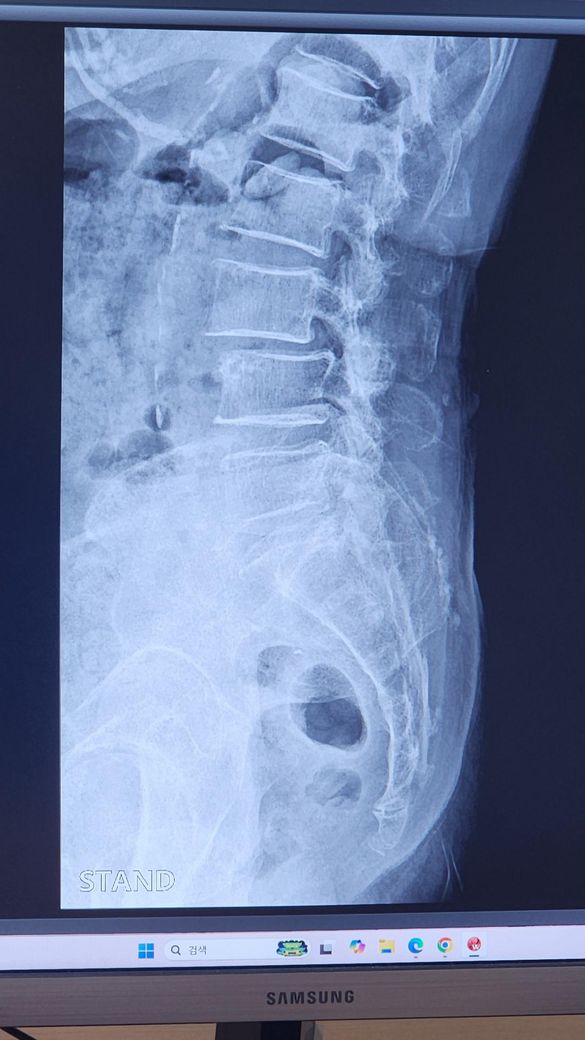

할머니께서 척추전방전위 진단을 받으셨습니다

할머니가 의료급여지원을 받고계셔서 지정한 병원만 다니는데 오른쪽다리가 많이 저려서 주사치료를 받았지만 진전이없어서 다른병원가서 진단받아보니 척추전방전위 진단을 받았습니다. 이것때문에 협착증이 같이와서 주사치료를 받아도 크게 의미없다고해서 mri를 찍어보고 시술을할지 수술을할지 정하자고합니다.

그치만 동네병원에서 서류를 떼어주면서 어차피 협착증이라 할것이고 시술이나 수술하자고 권하실거다 자기네 병원에서 주사치료로 낫게 해드릴수있다해서 아버지가 고민을 하고계십니다. 한달정도 동네병원에서 치료를받을지 바로 mri를 예약할지 어떻게하면 좋을까요?